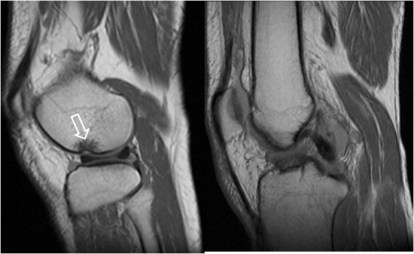

SIGNO DEL SURCO FEMORAL LATERAL

Signo indirecto de rotura del ligamento cruzado anterior (LCA) en la radiografía simple. Se trata de una depresión anormalmente profunda del surco cóndilo-patelar lateral o surco femoral lateral (flecha). Este surco es una pequeña depresión normal en la superficie articular del cóndilo, entre la curvatura que articula con la rótula y la que gira sobre la tibia. El surco anormalmente profundo se produce en la fractura osteocondral impactada, que acontece al tiempo que la rotura del LCA, ya que el mecanismo de ambas lesiones es el mismo: rotación de la articulación y valgo forzado, en el que chocan el platillo tibial contra el cóndilo femoral.

Imágenes de resonancia magnética de la rodilla, que muestran cortes sagitales de una secuencia potenciada en T1. La fotografía de la izquierda muestra como el surco femoral lateral es anormalmente profundo y se acompaña de una disminución de la señal del hueso adyacente por edema medular (flecha blanca). A la derecha, corte en el que debería verse el LCA, ausente por rotura.